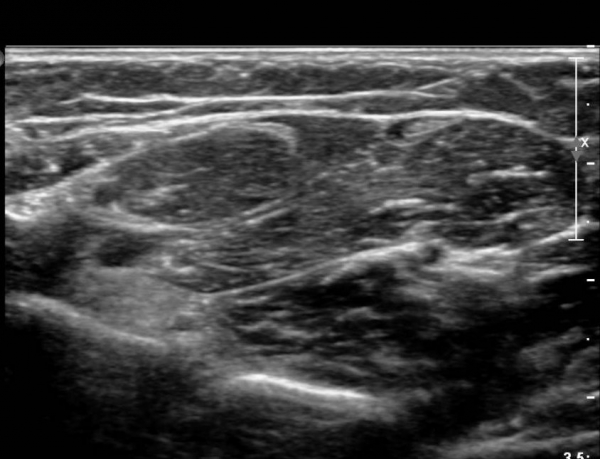

¾Æ·§ÆÈ¿¡¼­ Àü°ñ°£ ½Å°æºÎÀ§ Ⱦ´Ü¸é°Ë»ç»ó ¾öÁö ±¼±ÙÀÇ °í¿¡ÄÚ º¯¼ºÀÌ °üÂûµÇ°í  Àü°ñ°£µ¿¸Æ

ÁÖÀ§¿¡¼­ Á¾±« µî Ưº°ÇÑ ÀÌ»ó ¼Ò°ßÀÌ °üÂûµÇÁö ¾Ê´Â´Ù(»çÁø 1).